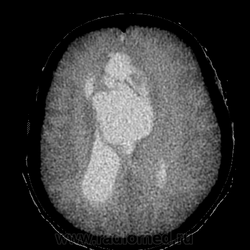

Кстати насчёт шутки. Это же негатив КТ вместо МРТ?

Да, это негатив КТ, специально для Танюши, чтобы проще сориентироватся.

Больному около 55 лет, клинику дает не сколько само образование, а компрессия структур мозга, базально вообще беда (отчасти видно компреммию некоторых базальных цистерн мозга). Сразу скажу насчет эпидермоидной кисты - ДВИ не будет :)

Однозначно киста, значит, осталось выяснить какая, холестеатома или арахноидальная?

Все-таки лучше сделать МРТ. А то нейрохирурги быстро ножи наточат;)